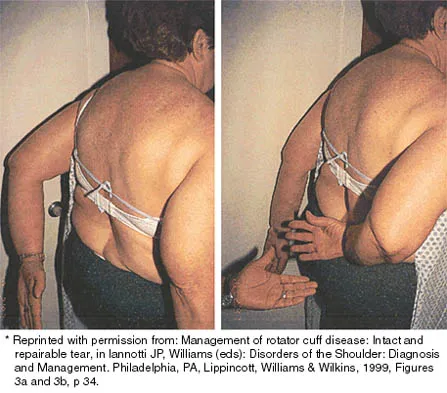

Initial postoperative management after repair of an acute rotator cuff tear includes

Explanation